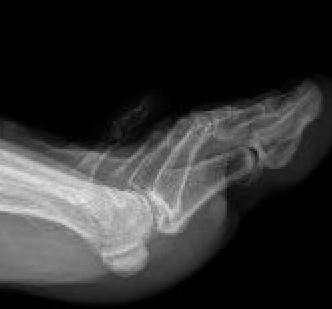

5th toe adducted & overrides 4th toe

Dorsomedial subluxation of the MTPJ

Racquet shaped incision dorsally

- preserve NV bundles

- EDL and dorsal capsule divided

- toe swung back into position and sutured